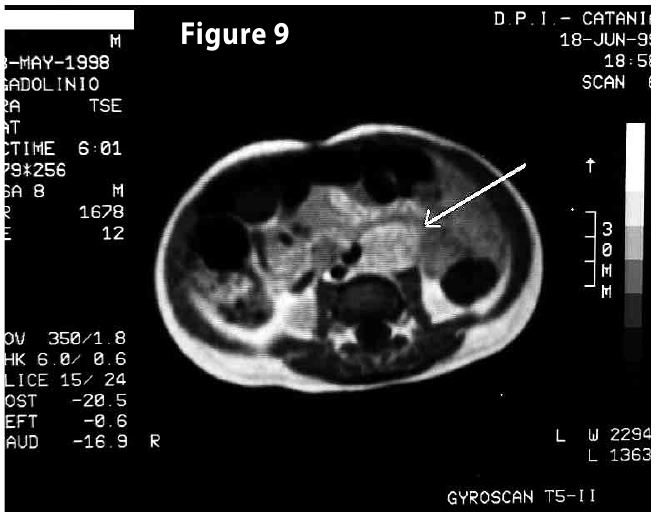

Figure9